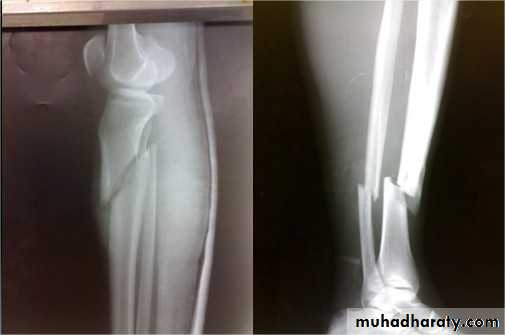

Fractures of the tibia and fibulaIndirect force: (low energy)

Twisting: spiral fractures of both bones

Angulatory: oblique fractures with butterfly segment.

Direct force:

Transverse (low energy) or comminuted (high energy) fractures usually with skin and soft tissue damage.

Skeletal fixation

Locked intramedullary fixation is the method of choice for diaphyseal (shaft) fractures.

Plate and screws for fractures near bone ends (metaphyseal) and for children with closed unstable fractures.